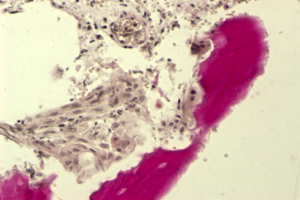

1. Очистка и обработка материала. Получение биоиплантата "Лиопласт"

6. Полное замещение биоимплантатов собственными тканями организма